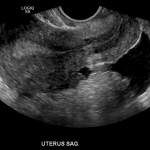

- Peripherally-enhancing structure in the right ovary with crenulated margins

- Moderate volume hemoperitoneum layering in the anatomic pelvis

- Ruptured ovarian cyst

Moderate hemoperitoneum likely from a ruptured ovarian cyst. Higher density blood clot adjacent to a right ovarian corpus luteal cyst favors this as the causative lesion.